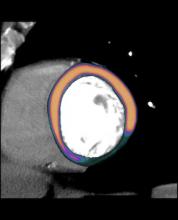

The next big advancement in cardiac imaging is likely to be computed tomography (CT) perfusion imaging. This enables one commonly available modality to image both the detailed anatomy and function of the heart at the same time. The impact on medicine could reduce healthcare costs by eliminating some hospital stays, cutting the number of tests and speeding patient diagnosis.